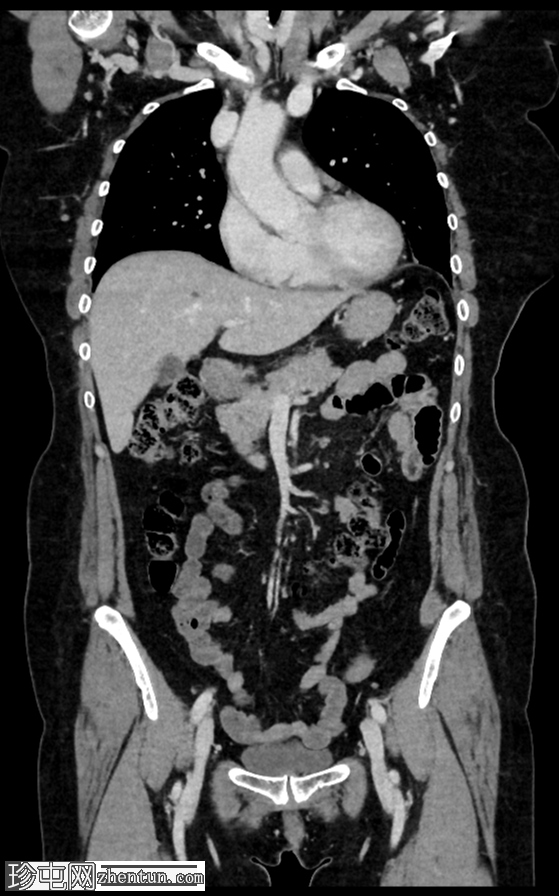

冠状位增强扫描

门静脉期

右肾上极前外侧可见一边界清晰、分叶状、部分外生性病变,大小约4.0 x 6.8 cm(轴位)。病变内侧为无强化囊性成分,直径2.3 cm(动脉期和门静脉期平均密度均为13 HU);外侧为强化实性成分,直径4.5 cm(动脉期和门静脉期平均密度分别为68 HU和78 HU)。病灶内可见多处小钙化灶。病灶毗邻肝右叶,但未见侵犯肝实质的证据。肾静脉和下腔静脉通畅。肾门水平可见数个小的主动脉腔静脉淋巴结和腔静脉后淋巴结,其中最大的腔静脉后淋巴结短轴直径为7毫米。

右肾中极前缘可见10毫米Bosniak II型囊肿,双侧肾盂旁可见囊肿。右肾下极可见两处肾皮质缺损。肝脏第8段可见5毫米囊肿。未见远处转移。L2椎体可见血管瘤。